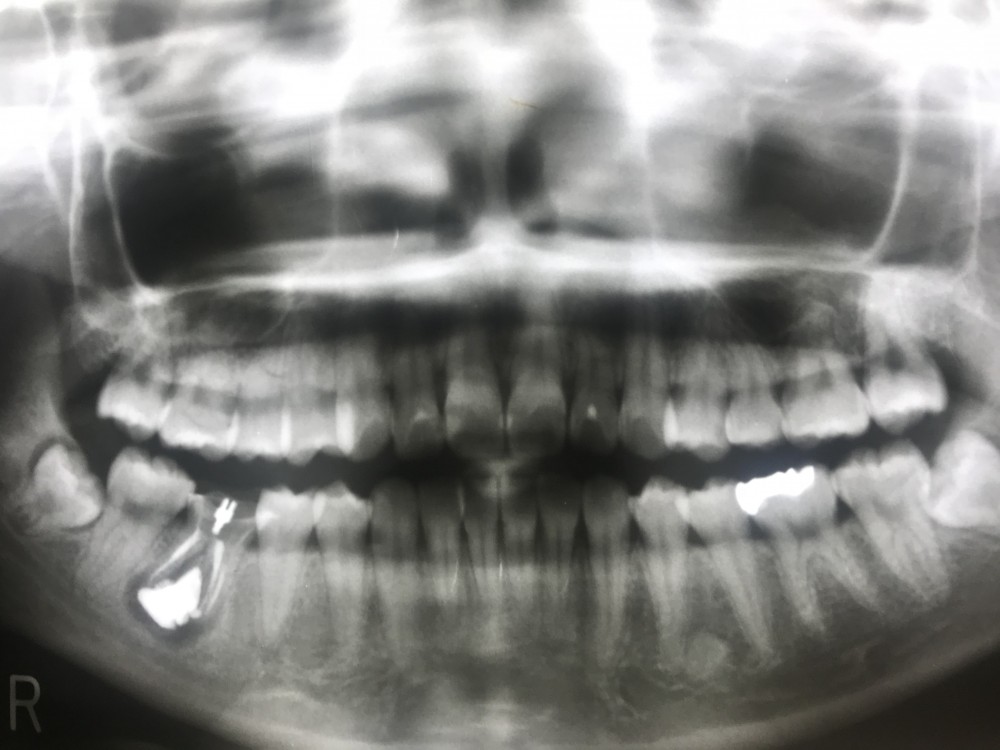

下の画像は初診時から1ヶ月後のもの。根管治療、ビタペックス貼薬、ポストテックセットしています。

1〜3ヶ月おきに経過観察、症状ない事を確認